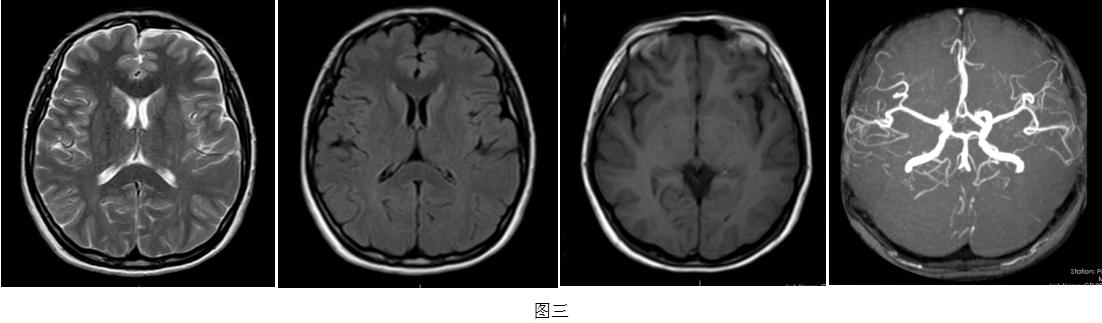

广东三九脑科医院神经内二科主任钟水生接诊后,为患者完善专科查体,结果都正常。入院后完善右心声学造影:静息状态下3-6个周期内,房水平右向左分流3级,Valsalva动作释放时,房水平3-6个周期内左房、左室可见持续性浓密造影剂气泡回声,静息状态及Valsalva动作房水平右向左分流均3级,考虑存在卵圆孔未闭可能性大(图一)。TCD发泡试验阳性,支持右向左分流(图二)。心脏彩超:心脏未见异常。进一步完善头颅MR平扫+半球动脉(MRA) 示部分空蝶鞍,右侧大脑前动脉A1段发育不良(图三)。